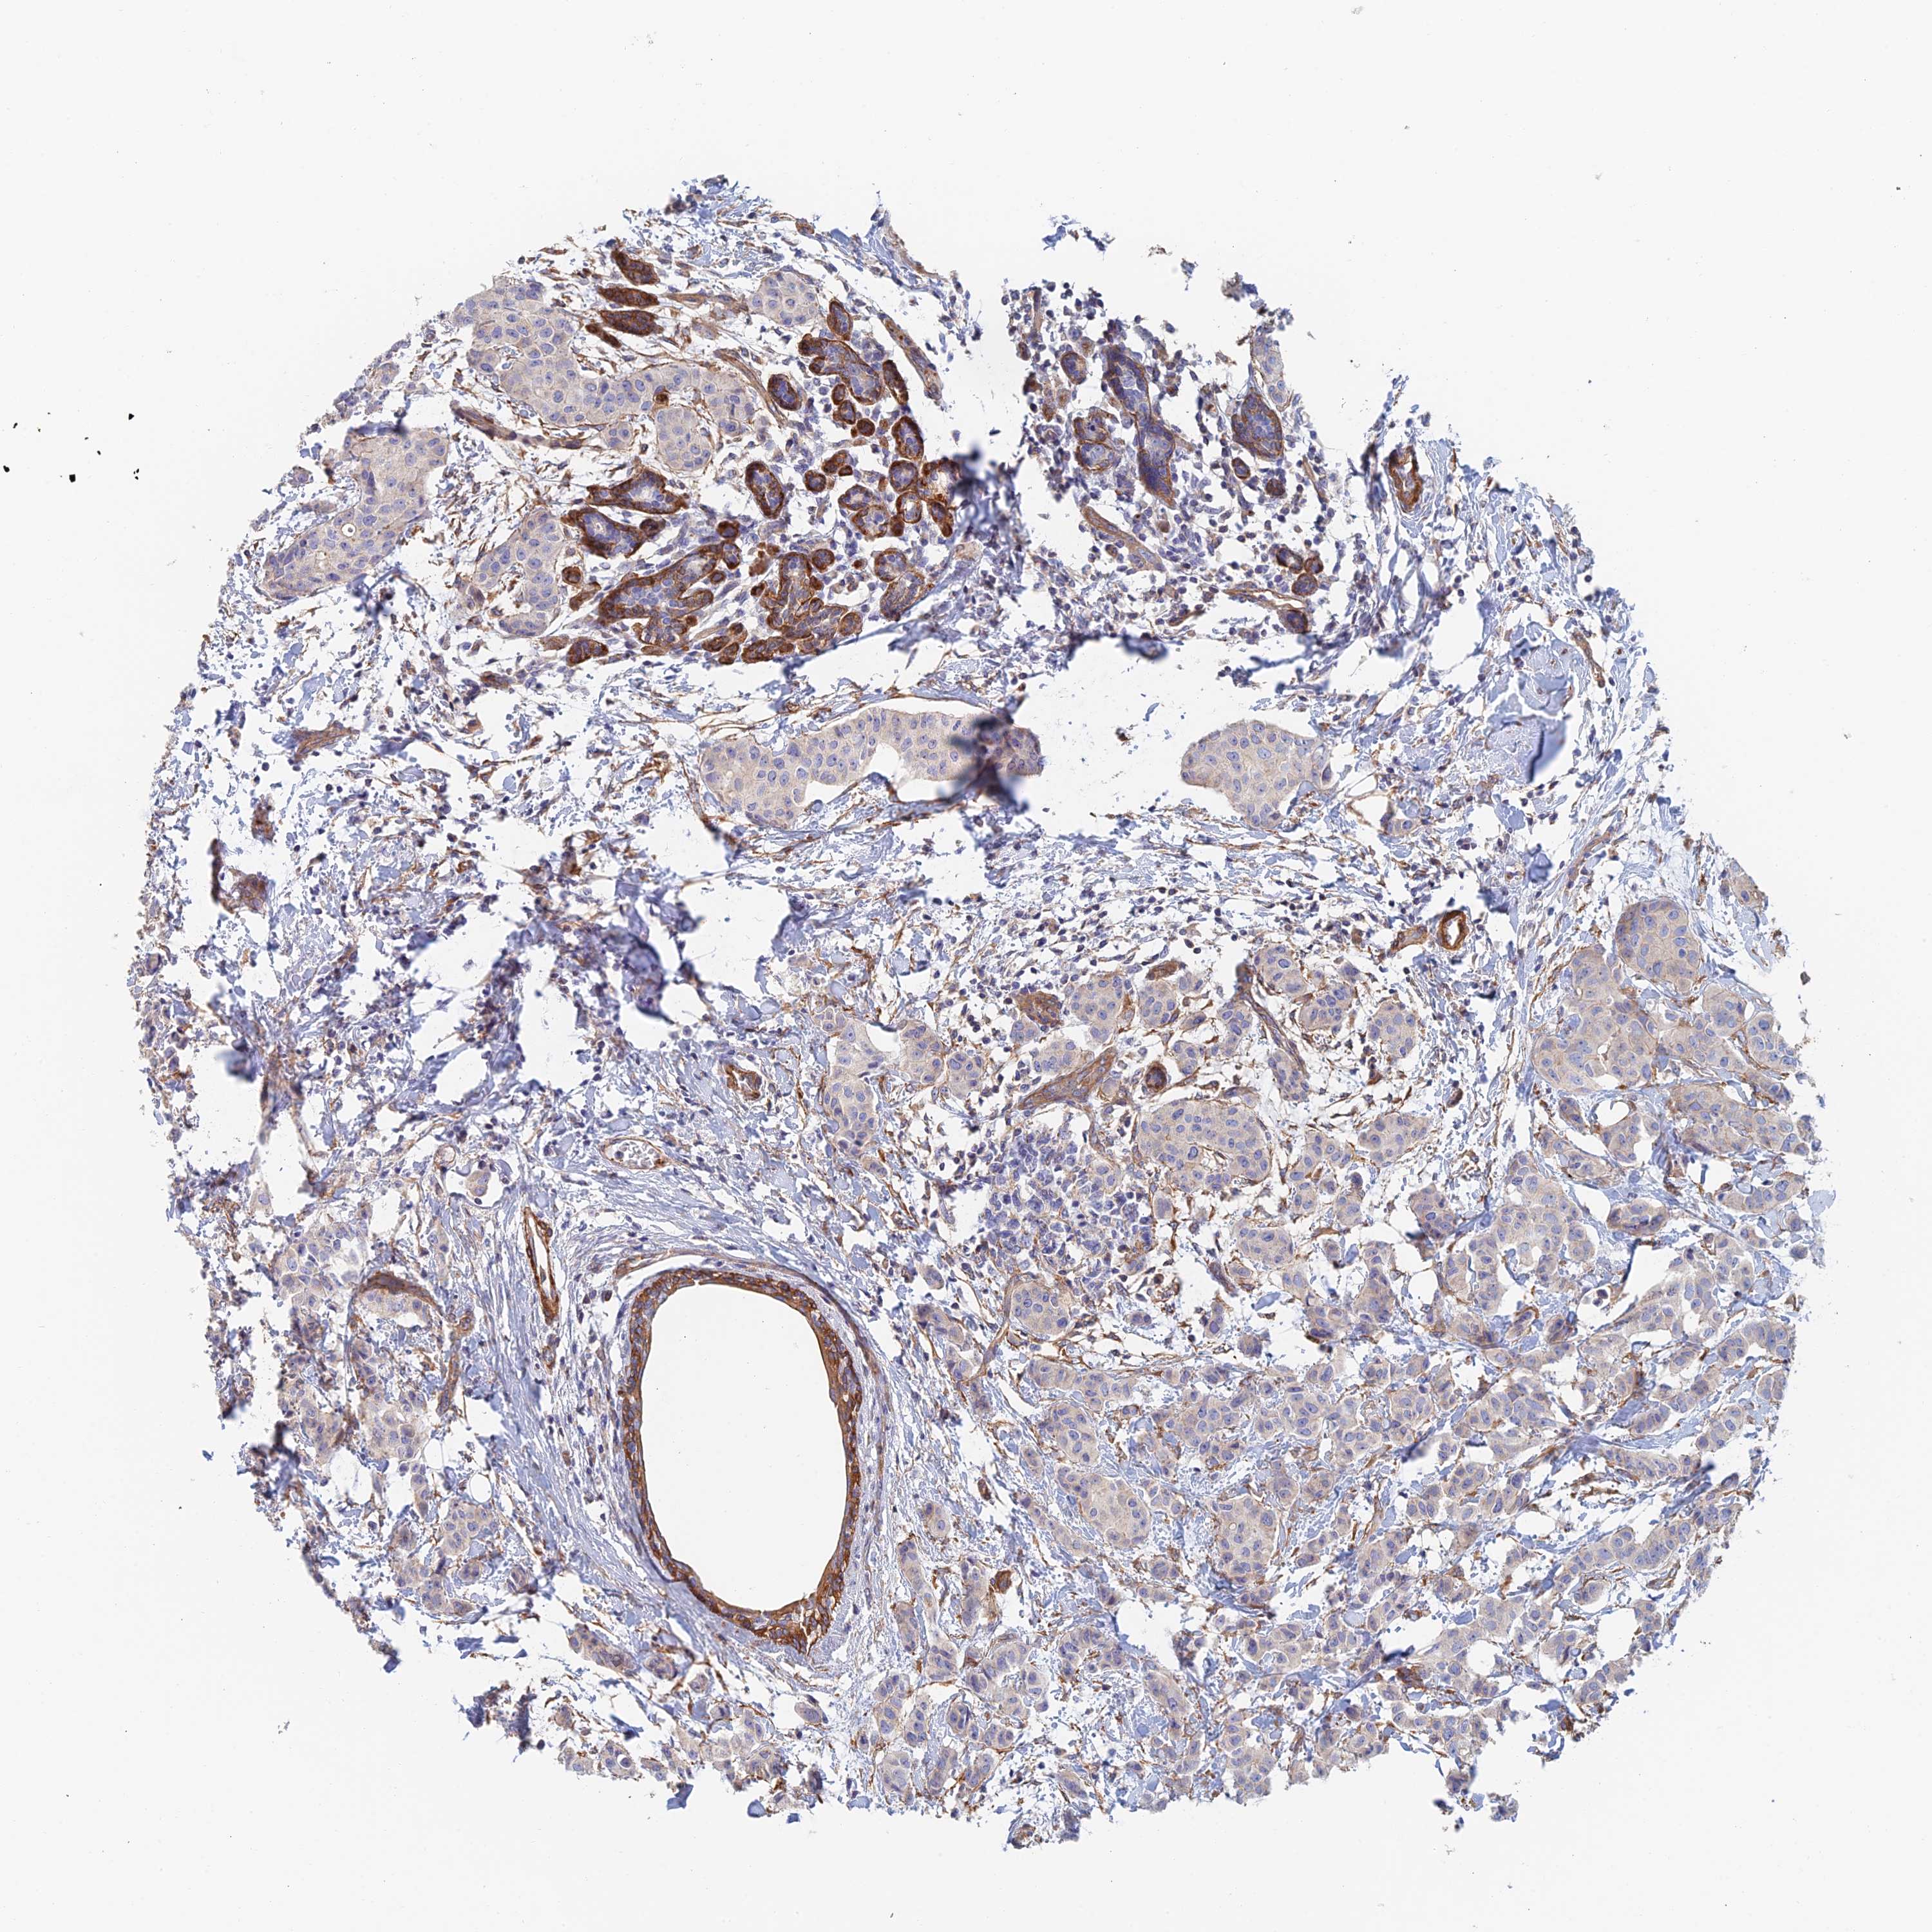

CANCER BREAST CANCER Show tissue menu

BRCA TCGA BRCA VALIDATION PROTEIN EXPRESSION

Breast cancer

Human cancer